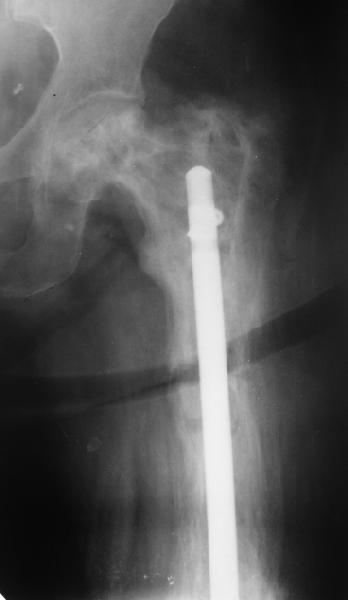

Еще один пример. Пациентка с юга России, прислала рентгенограммы через

год. На сегодня прошло 2 г. 8 мес. после операции. Несмотря на не очень

убедительный процесс сращения, пациентка ходит. Учитывая остеопороз при

Педжете, решили, что динамизировать вообще не нужно.